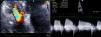

Apresentamos o caso de uma mulher de 80 anos, portadora de pacemaker definitivo modo VDD desde 2001 por doença do tecido de condução sintomática que foi submetida a substituição do gerador por exaustão do mesmo em fevereiro de 2009. Em agosto de 2010 recorreu ao serviço de urgência por quadro clínico com 2 meses de evolução e em agravamento progressivo de dispneia de esforço classe iii/iv NYHA, ortopneia, edemas, dor abdominal de predomínio nos quadrantes direitos, astenia e anorexia. Ao exame objetivo apresentava distensão venosa jugular, cianose facial, edemas generalizados, hepatomegalia, pulso periférico irregular e rápido, auscultação pulmonar sem sinais de estase, sons cardíacos hipofonéticos e sopro mesossistólico aórtico e diastólico de baixa frequência no bordo esternal esquerdo. O eletrocardiograma mostrou fibrilação auricular com resposta controlada alternando com ritmo de pacemaker ventricular. A radiografia de tórax revelou cardiomegalia, apagamento dos fundos de saco e um anel redundante do eletrocateter ventricular ao nível do aparelho valvular tricúspide, sem outras alterações relevantes (figura 3A). No estudo analítico foi detetada ligeira elevação do BNP e de γ-GT, sem outras alterações dignas de registo. O ecocardiograma revelou folhetos da VT espessados e eletrocateter ventricular aderente ao aparelho valvular e subvalvular a condicionar limitação grave da sua amplitude de abertura (gradientes máximo e médio de 15 e 10mmHg e área funcional estimada em 0,6 cm2) (figura 4), esclerose aórtica e derrame pericárdico de médio volume ao nível da parede livre do ventrículo esquerdo (1,6cm) e de grande volume na parede do ventrículo direito (2,4-2,1cm) com ligeiro colapso diastólico do ventrículo direito (figura 3B). O cateterismo cardíaco direito mostrou anormal posicionamento do eletrocateter de pacemaker no seu percurso valvular tricúspide e VT deformada, com abertura excêntrica de amplitude reduzida e gradiente médio 11mmHg) (figura 5). O cateterismo esquerdo revelou válvula aórtica deformada e calcificada com gradiente máximo ventrículo-aórtico de 13mmHg, função ventricular esquerda conservada – fração de ejeção de 62%) e coronárias com doença aterosclerótica parietal calcificada sem evidência de estenoses significativas. Transferida para centro de Cirurgia Cardiotorácica, onde após avaliação foi decidido efetuar pericardiocentese evacuadora associada a optimização da terapêutica médica. Dada a evolução sintomática favorável foi proposta terapêutica conservadora com posterior reavaliação da necessidade de intervenção cirúrgica. Seis meses após a alta a doente encontra-se em classe funcional ii/iv NYHA e apresenta ecocardiograma com ET severa e estenose aórtica ligeira, sem derrame pericárdico.